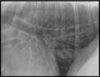

Q

VD